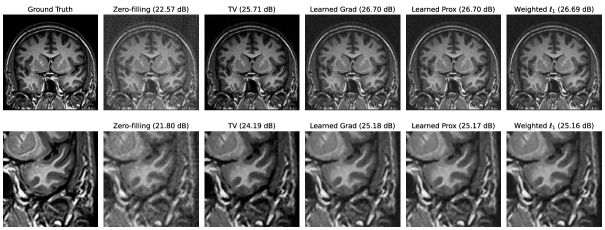

For validation purposes, we applied our framework to the denoising of natural images and to the reconstruction of magnetic resonance data.

• [80] G. M. Ziegler, Lectures on Polytopes, vol. 152, Springer Science & Business Media, 2012.